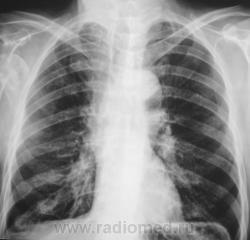

Перелом шейки правой плечевой кости вижу. Свежих переломов ребер и пневмоторакса не вижу. Справа - старые переломы. Но, честно говоря, видно плохо - снимки почему-то не увеличиваются...

Вы правы, структура не нормальна, есть довольно четкие очаги. Аналогичный очаг в суставном отростке лопатки, да и структура задних отрезков 9-10 ребер справа настораживает. Перелом плеча, если он действительно свежий, то скорее всего - патологический. Но! А травмы кисти и л/з сустава не было?

Лаборанты "усекли", что что-то не в порядке с головкой плечевой кости и с самой плечевой костью и решили дополнительно сделать рентгенограмму сустава.

Похоже тоже старый неконсолидорованый переломовывих. А переломов ребер и тут не вижу...

Перелом, по всей видимости, не старый, травма 2 дня тому, но "клиент" находился в подпитии.

Большой интерес, конечно, представляет "ручка", левая клиента. Какой-то уж сильно странненький остеопороз.